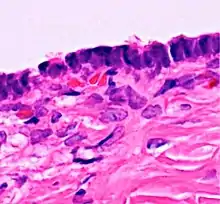

![]() | Serous cystadenoma | Histopathology of serous cystadenoma, with admixed scattered ciliated cells. This case closely resembles normal surface endometrial epithelium of the uterus | Category: Histopathology of ovarian serous cystadenoma | Ovarian cystadenoma |